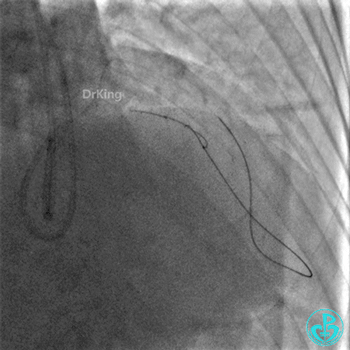

EBU指引导管左冠脉造影显示粗大前降支中段闭塞,闭塞段近端有对角支发出,前降支同侧逆向显影,闭塞段不长。